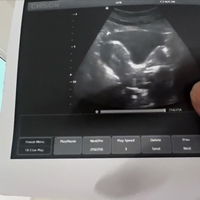

alhamdulillah tak ada alahan teruk. cuma tak lalu nak makan. tengok nasi jadi muak. paksa makan nasi pon rasa nak muntah. 😂 skrg dah 6w5d. baru buat scan td. dah nampak kantung dgn heart beat.